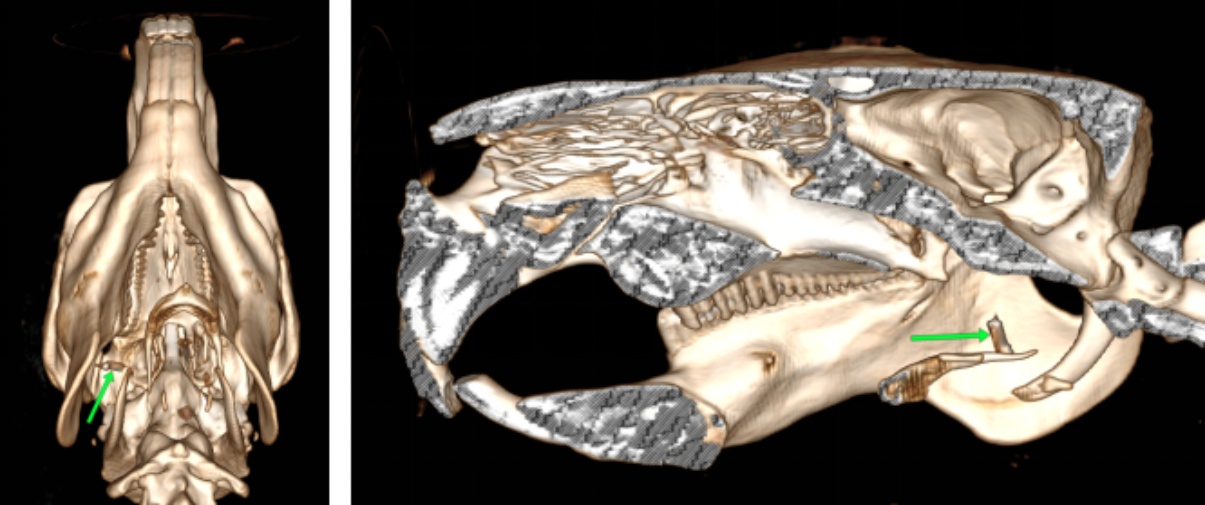

使用万东医疗的OpenCT机,将患病水豚以背卧位及侧卧位保定进行头部平扫和三维成像,影像结果见图1图2

图1(A)可知,其右侧喉咽部会厌水平处有一细棒状金属密度异物影,长度约1.8 cm,周围软组织密度降低,软组织内有多个小气泡影。由图1(B)可知其双侧颞下颌关节未有明显脱位。由图1(C)可知,其右侧鼓室重力侧有层状中等密度影,左侧鼓室内充满气体影,外耳道通畅,耳道壁有点状钙化灶。各牙齿密度正常,齿根处无明显骨质溶解,未有齿根过长,双侧切齿对合良好。脑中线居中,脑实质无明显异常密度影。鼻中隔居中,筛骨完整、对称,鼻腔内无明显渗出影。

Figure 1. CT image of diseased capybara

1. 患病水豚CT影像

Figure 2. Three-dimensional imaging of diseased capybara

2. 患病水豚三维成像